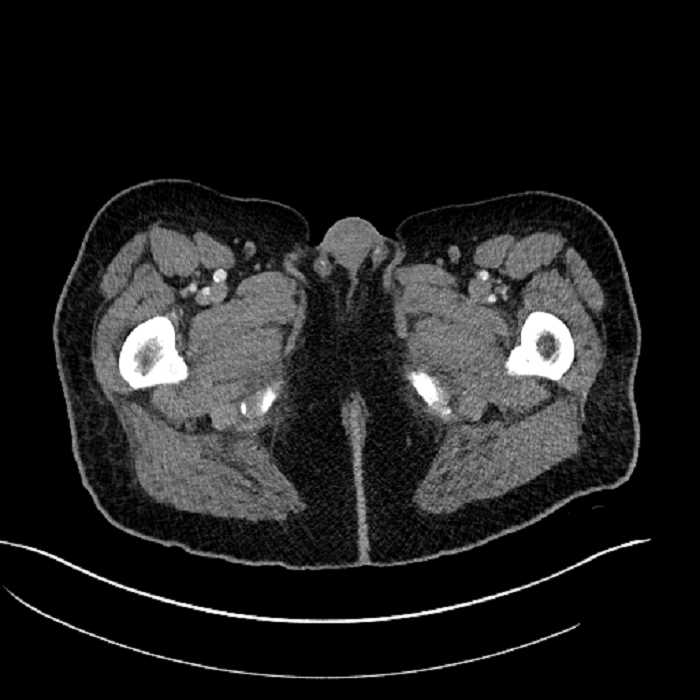

• High grade stenosis of the left common iliac artery, with the left internal and external iliac arteries remaining patent

• Ankylosis of both sacroiliac joints

High grade stenosis of the left common iliac artery. The left external and internal iliac arteries are patent.